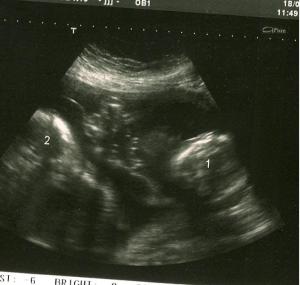

Quelques jours plus tard j’ai fait un test qui s’est avéré positif. J’étais heureuse, mais un peu sous le choc. Nous l’avons annoncé à la famille durant le temps des fêtes. Je commençais à peine à réaliser que je portais la vie lorsque je suis arrivée à mon premier rendez-vous avec ma gynécologue. J’étais alors enceinte de 11 semaines et 3 jours. Ma gynéco me fait les tests de routine, écoute le cœur du bébé et me fait une petite échographie pour me montrer de quoi ça a l’air. Elle pointe l’écran et dit : «Regardez ici on voit bien la poche et… il y en a deux…». Sur l’écran je voyais deux petites poches. Mon chum n’a pas compris tout de suite, il a même demandé «deux quoi ?» et moi je me suis tout simplement dit «ha ok !». Le médecin a dû nous trouver poche, on n’a pas eu de réaction. Il n’y a aucun jumeaux dans notre famille ou dans notre entourage, donc nous n’avions jamais envisagé que cela puisse nous arriver. C’est probablement pour ça qu’on ne réagissait pas, nous étions sous le choc, encore une fois. En sortant de la clinique, je me suis mise à paniquer un peu. J’ai dit à mon amoureux «Comment on va faire avec deux bébés? Est-ce qu’on a les moyens de tout acheter en double?». Il m’a répondu avec son calme légendaire que tout irait bien. Nous sommes alors allés directement chez ma mère pour lui annoncer la nouvelle. Avant d’aller chez elle je l’ai appelé à son travail pour lui demander si elle pouvait aller diner chez elle, que je voulais lui parler de mon rendez-vous. Tout de suite, elle m’a demandé si tout était correct. Je l’ai rassurée et en terminant l’appel elle m’a lancé : « Il y a juste un bébé?». Encore aujourd’hui, elle ne sait pas ce qui l’a poussée à dire cela, comme je l’ai metionné plus tôt, nous n’avions jamais parlé de la possibilité d’avoir des jumeaux. Bref, après ma mère nous sommes allés l’annoncer à mes beaux-parents et à ma belle-soeur. Lorsqu’ils ont fini par nous croire, tout le monde a très bien accueuilli la nouvelle. À la fin de cette journée, mes craintes étaient disparues et j’étais bien heureuse de pouvoir vivre cette expérience unique.